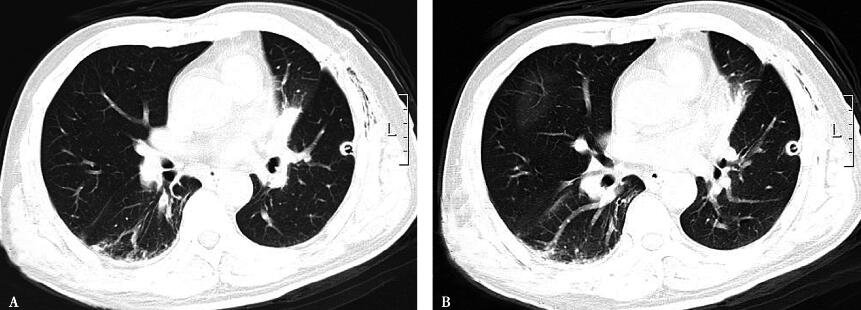

(二)疗效

治疗1周后,患者无发热,复查胸部CT(图5)提示肺部团块影明显吸收。患者要求出院,嘱出院后继续用药,改为氟康唑400mg,每日1次,口服序贯治疗,门诊复查。

图5